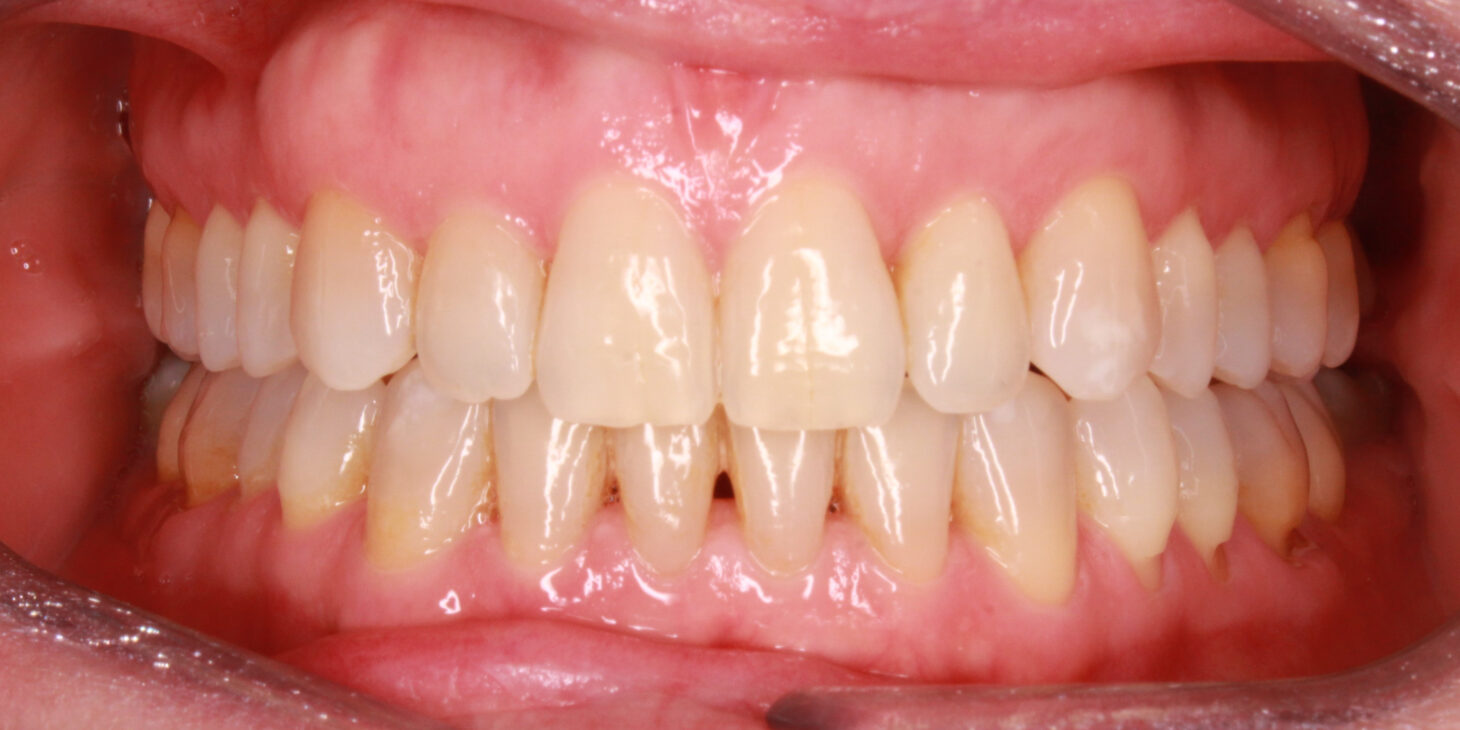

At the end of the primary treatment plan the patient returns to the office and we can see that, although the vertical plan has been favored thanks to the planned movements, the midlines are centered, and the crowding has improved notably and with it the periodontal status of the patient.

After 8 months of the primary treatment plan and the refinement, it was possible to observe a fulfillment of the objectives demanded by the patient and clinically marked at the time of the initial diagnosis.